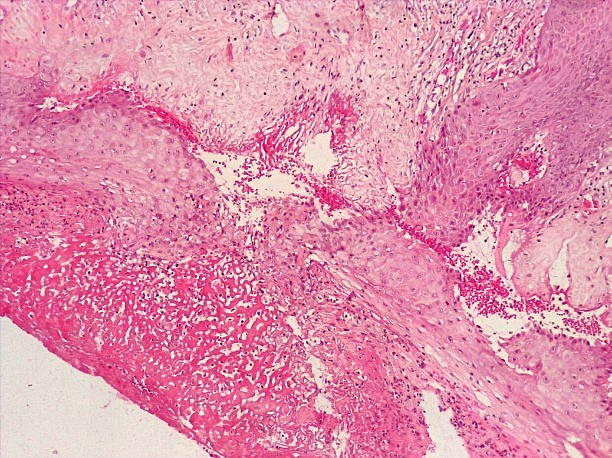

При проведении морфологического исследования тканей вульвы пациенток со склероатрофическим вариантом течения СЛВ также отмечалась резкая атрофия кожи за счет клеток эпидермиса и дермы, уменьшение клеточных слоев эпидермиса от 2–3 до 4–5 с участками повышенного ороговения (гипрекератоз). Количество базального слоя было снижено в разных случаях от 2–3 до 5–6 клеток в 1 мкм, что указывало на снижение функционального резерва эпидермиса. В случае длительного течения заболевания клетки базального слоя имели признаки дистрофии. В поверхностных слоях дермы отмечался фиброз с отложением масс гиалина, а также редукция кровеносных сосудов мелкого калибра, окруженных клеточным воспалительным инфильтратом из лимфоцитов и макрофагов (рис. 14–17).

Рис.14. Склероатрофический вариант СЛ. Резкая атрофия клеток эпидермиса с участками повышенного ороговения с развитием фиброзной соединительной ткани с лимфо-гистиоцитарной инфильтрацией дермы (окраска гематоксилином-эозином, х100).

Fig.14. Scleroatrophic variant of SL. Sharp atrophy of epidermal cells with areas of increased keratinization with the development of fibrous connective tissue with lympho-histiocytic infiltration of the dermis (hematoxylin-eosin staining, x 100)